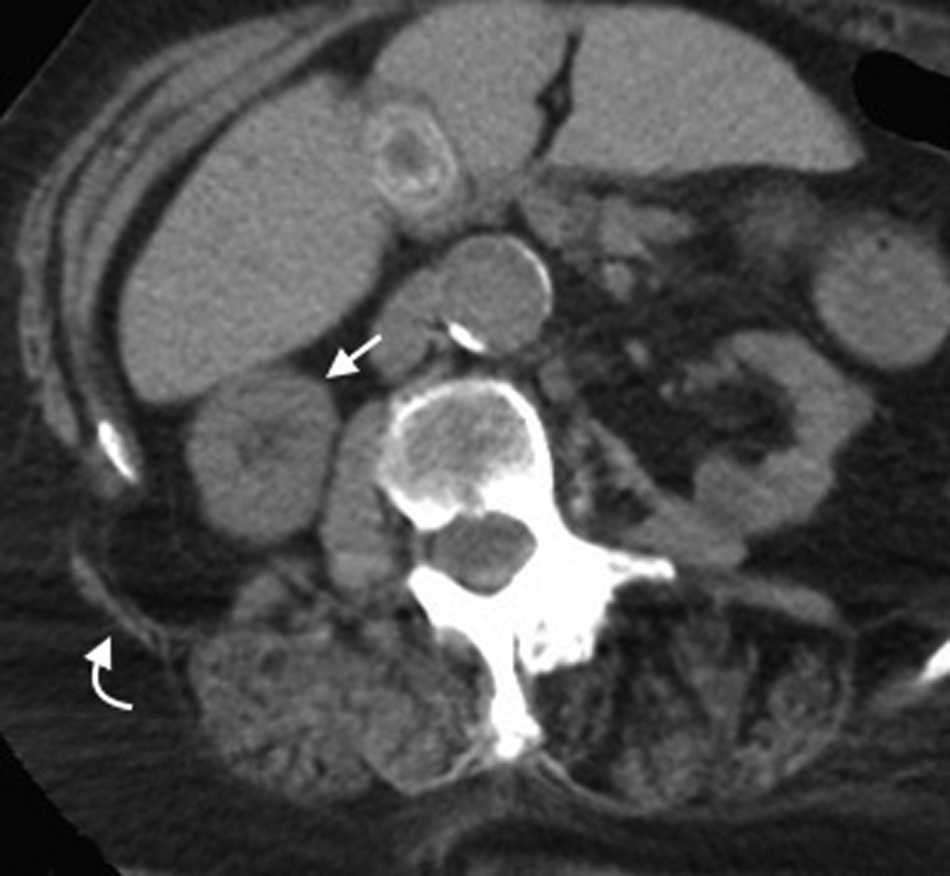

Hernia de Spiegel

Es una hernia ventral adquirida poco frecuente4. Ocurre por un defecto en la aponeurosis de los m??sculos oblicuo interno y transverso abdominal, y tiene una localizaci??n caracter??stica en la uni??n de las l??neas semilunar y semicircular o arqueada3. Es lateral al recto anterior del abdomen e inferior al ombligo, y casi siempre se encuentra justo por encima del punto en el que los vasos epig??stricos inferiores perforan la pared posterior de la vaina del m??sculo recto del abdomen1.

Su diagn??stico cl??nico no es f??cil porque esta hernia se extiende entre las capas musculares o fasciales de la pared abdominal anterior. El orificio herniario puede ser peque??o, dif??cil de localizar y tener grasa omental (fig. 5a), asas de intestino delgado (fig. 5b) o implantes metast??sicos12 (fig. 6).